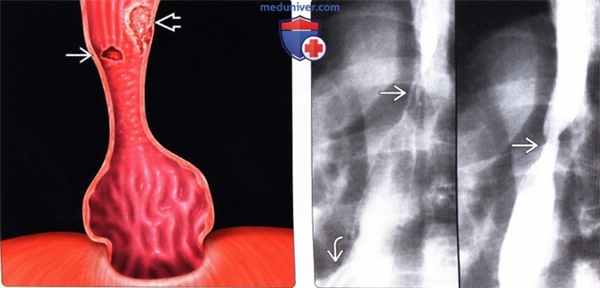

Рентгенограмма при пищеводе Барретта

2. Рентгенография при пищеводе Барретта:

• Метод выбора: рентгеноскопия пищевода с двойным контрастированием

• На основании изменений, выявленных при эндоскопии и гистологическом исследовании, выделяют два типа пищевода Барретта:

о Длинный пищевод Барретта: цилиндрический эпителий слизистой оболочки протяженностью более чем 3 см от уровня пищеводно-желудочного перехода:

- Обычно возникает вследствие более тяжелого течения ГЭРБ

- Грыжа пищеводного отверстия диафрагмы практически у всех пациентов

- Неправильный контур слизистой оболочки в средних отделах пищевода, стриктура, изъязвление

- Риск возникновения рака пищевода выше, чем при коротком пищеводе Барретта

о Короткий пищевод Барретта: цилиндрический эпителий протяженностью - Возникает при более легком течении ГЭРБ

- Грыжа пищеводного отверстия диафрагмы возникает у 72% пациентов

(Слева) На схеме показаны грыжа пищеводного отверстия диафрагмы первого типа, стриктура дистальных отделов пищевода и множественные узелки на поверхности слизистой оболочки. Обратите внимание на отдельно лежащую язву, а также аденокарциному — приподнятое над поверхностью объемное образование с неровными краями, широким основанием прилежащее К'слизистой оболочке.

(Справа) На двух рентгенограммах, полученных при рентгеноскопии пищевода, определяется стриктура в его средних отделах, а также язва — у пациента с небольшой грыжей пищеводного отверстия диафрагмы и гастроэзофагеальным рефлюксом.